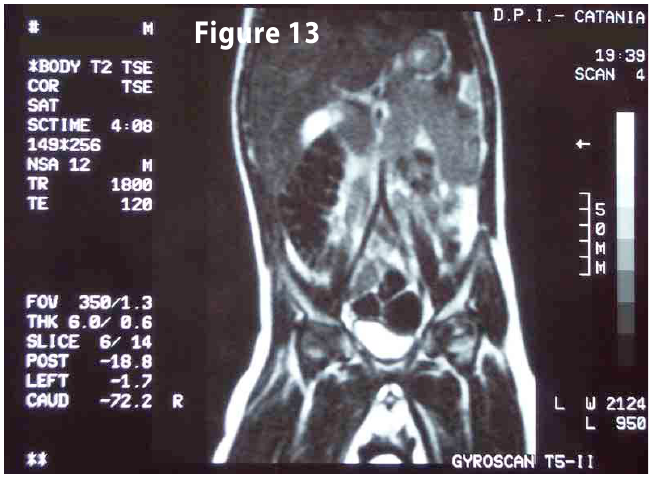

Complete objective response of neuroblastoma to biological treatment.

Figure13